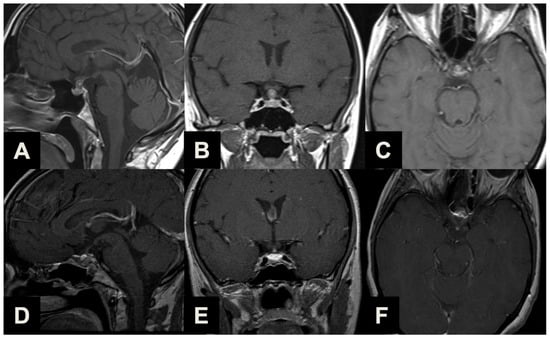

| Type 1 | Ectopic peduncular or supradiaphragmatic peri-infundibular PAs, including ectopic microadenomas of the pituitary stalk or purely supradiaphragmatic macroadenomas (mostly remnant or recurrence after previous partial surgeries). These tumors are not suitable for an EEA because they have no sellar infradiaphragmatic component. |

| Type 2 | PAs with sub-frontal extension, including macroadenomas with a supra- or infradiaphragmatic sub-frontal extension. These tumors are not fully resectable with an EEA because of their sub-frontal component, which extends anteriorly with an unfavorable angle and direction for the trans-sphenoidal approach. |

| Type 3 | PAs presenting with a major extrasellar component, including macroadenomas with suprasellar supradiaphragmatic component exceeding the sellar volume (i.e., air balloon PAs) unlikely to be delivered through the sella with an EEA, and macroadenomas with both a large intrasellar infradiaphragmatic part and a large suprasellar supradiaphragmatic portion connected through a narrow isthmus (i.e., snowman PAs), which impairs their resection through an EEA. |